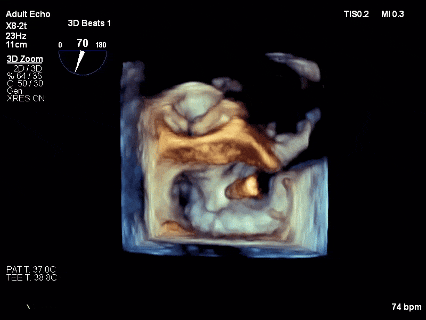

最终结果3D-Zoom-color显示组织桥稳定,原脱垂区域前后叶对合部分的脱垂已消除,反流降至1+以下

夹子释放Bi-com切面显示残余反流情况

术后2D TTE:

术后TTE可见二尖瓣微量-轻度反流,三尖瓣反流明显改善降至中度